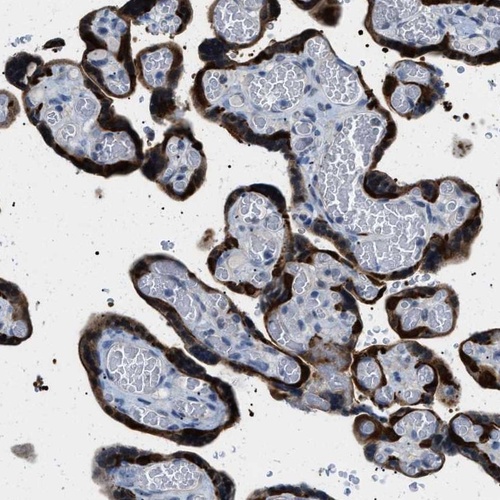

Immunohistochemical staining of human placenta shows strong cytoplasmic positivity in trophoblastic cells.